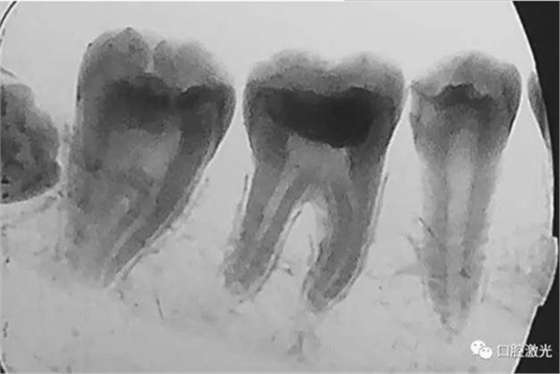

活髓理療治療結(jié)果令人滿意,沒有出血,也沒有出現(xiàn)碳化?;颊邲]有感受到不適并表示滿意。為了跟蹤激光輔助活髓切除術(shù)的治療效果,手術(shù)完成即刻和5周后分別拍攝了X光圖像。5周后的牙髓活性溫度測試也顯示陽性。

治療后5周